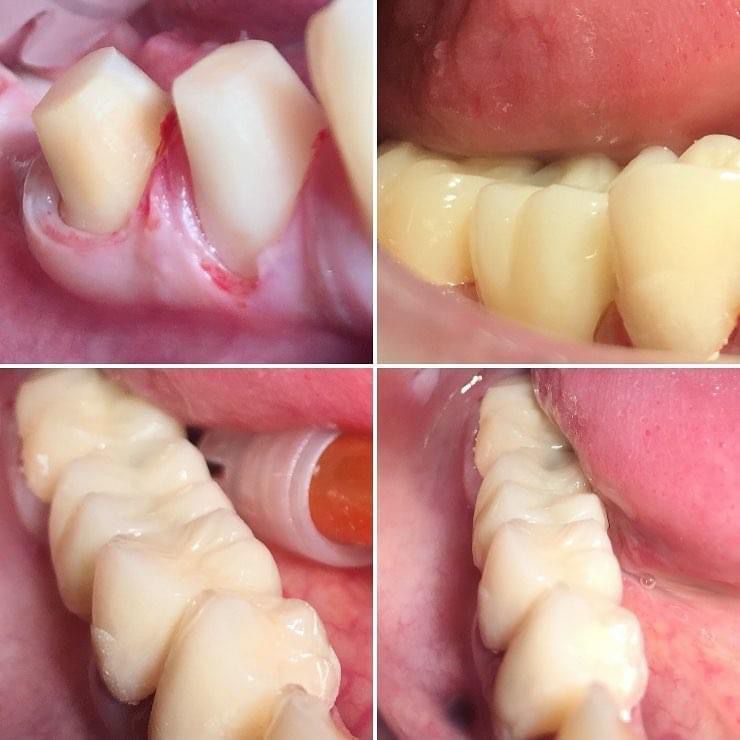

Foto e video